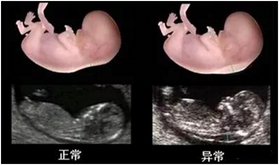

2、胎兒系統超聲檢查(四維大排畸:22-26周)

除了常規檢查以外,尚需要進行系統全面的胎兒超聲檢查,俗稱“大排畸”,以全面了解胎兒的生長發育情況。